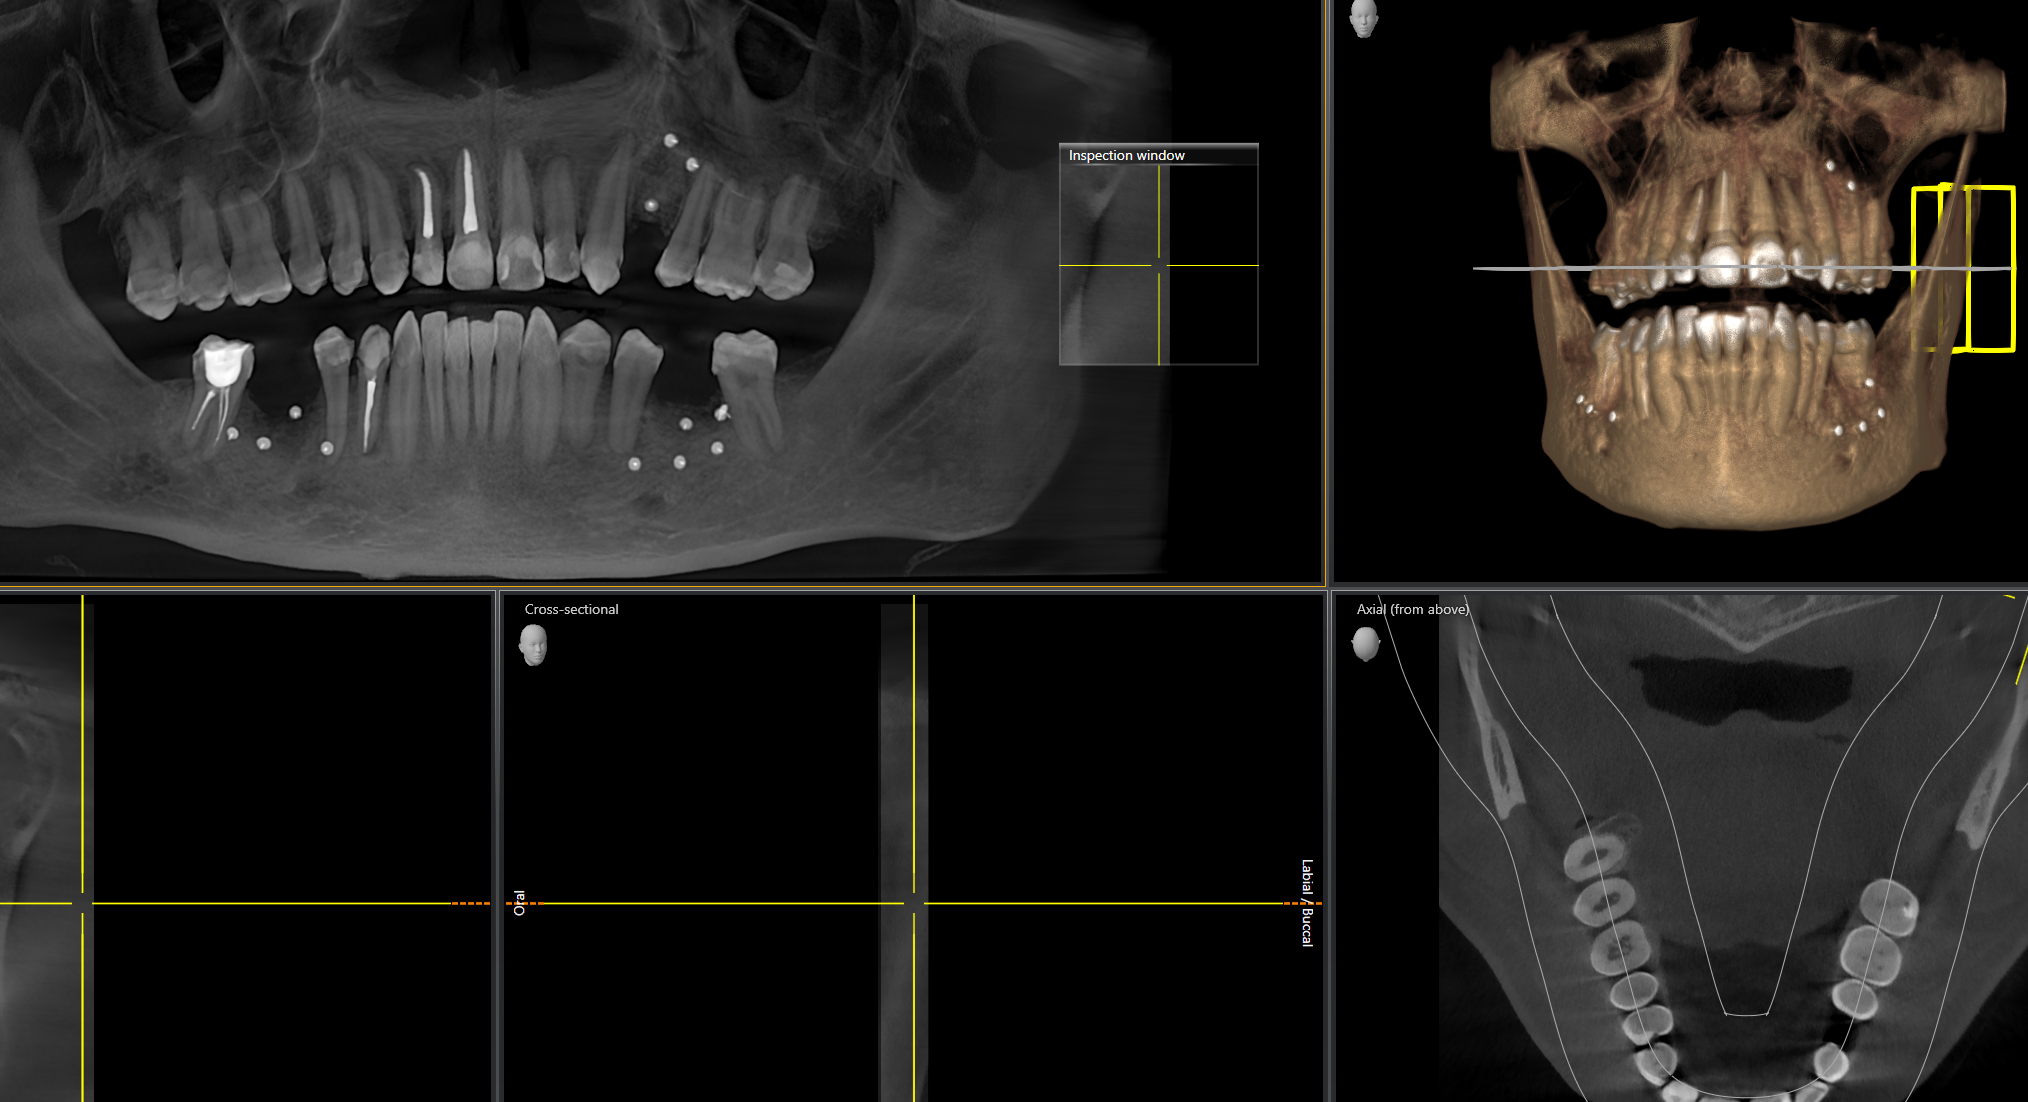

ОПУСТИЛИСЬ ДЁСНЫ, ОГОЛИЛИСЬ ШЕЙКИ ЗУБОВ 18/02/25 Втр 13:35:43 1602618 1

image 17Кб, 300x169

300x169

image 36Кб, 1024x616

1024x616

image 26Кб, 828x828

828x828

image 5Кб, 285x177

285x177

Сап медач.

Опустились дёсны в нескольких местах, обнажились шейки зубов. Чувствительные, болят от прикосновений, могут реагировать на холодное, горячее, сладкое.

Ситуация как примерно на пик2.